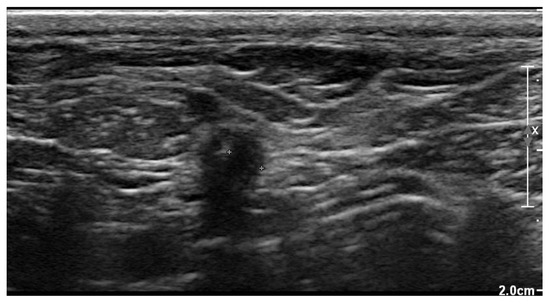

Three weeks after cessation of the oral antibiotic therapy, the dog became lethargic again and the owner noticed discharge from the previously healed cervical wound. The dog was presented again to the authors’ teaching hospital. Physical examination revealed a lethargic dog with a rectal temperature of 39.5 °C, and a warm and red lump of about 5 × 5 cm at the region of the previous surgical wound over the right jugular vein. In the skin overlying the lump, an opening of about 3 mm was visible, where purulent discharge was noticed. The dog was hospitalized again. Ultrasonographic examination of the lump was performed, which again identified a subcutaneous fluid pocket, but this time surrounded by a thick wall (Figure 7).

Figure 7. Two-dimensional grayscale ultrasonographic image of the swelling at the level of the previously healed surgical wound at the level of the jugular venous incision shows a pocket of fluid accumulation surrounded by abnormal soft tissue.

Under ultrasound-guidance, a puncture with a fine needle was performed, and the fluid was sampled. Special caution was exercised to prevent puncturing the pacemaker lead by visualizing it with ultrasound. The gained fluid sample was submitted for bacteriologic culture and cytologic examination. Cytology revealed exudative inflammation without visible bacteria. Repeated echocardiography did not reveal any signs of endocarditis. Due to the suspicion of persistent bacterial infection of the pacing lead, explantation of the pacing lead and the pulse generator was considered, and oral amoxicillin with clavulanic acid (10.7 mg/kg q12h) therapy was re-started. Explantation of the pacemaker seemed to be a safe option in this dog because the high-degree AV-block spontaneously resolved, and sinus rhythm was present. To ensure that the dog would function sufficiently without a pacemaker, the pulse generator was first switched off by programming it to OOO mode. Electrocardiography (ECG) revealed respiratory sinus arrhythmia with short periods of second- and third-degree AV-block with the lowest ventricular rate of 50 beats/min. The dog was discharged from the hospital with a Holter ECG for the weekend with the pacemaker in OOO mode. After the dog experienced a syncopal episode at home, it was brought back to the authors’ institution, and the pacemaker was switched on again and programmed in VVIR mode.